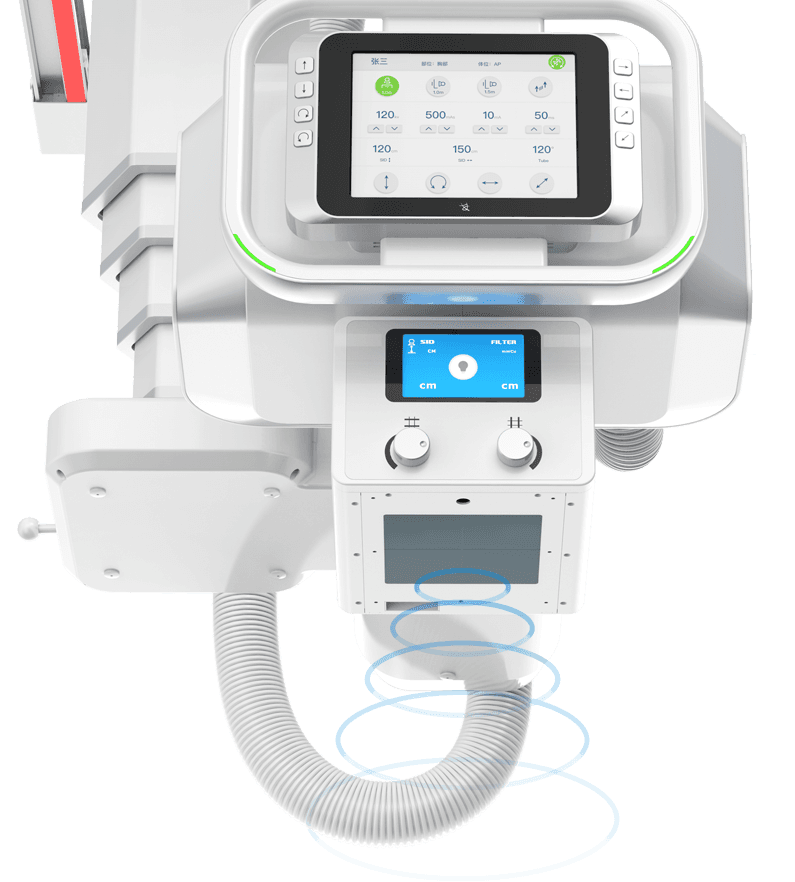

球管五向手自一体运动

采用手动与电动一体化设计,并具备感应驱动功能,

一键解锁即可轻松操控球管的全向运动。 -

智能触控大屏

液晶触摸屏,触摸操控设备运动,实时调整各类检查参数,

限束器智能缩窗

根据不同部位自动设置照射野,减少散射线及不必要的X光剂量,

提升影像质量。